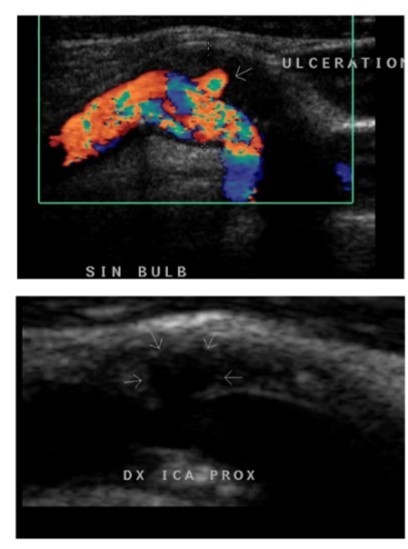

Vad kan vi se här?

Plaque yta/ruptur (se krater i undre bilden), färgdopplern sätts på och vi kan se att blod svirar runt